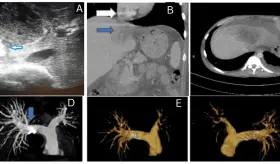

Las imágenes mostraron una aorta abdominal significativamente dilatada, con un diámetro transversal de 4.4 centímetros, muy por encima del límite normal de 3 centímetros.

Un caso de ruptura de absceso amébico en la vena cava inferior, con un trombo que se extiende hasta la aurícula derecha y tromboembolismo pulmonar tratado con éxito.

A pesar del tratamiento intervencionista exitoso mediante embolización, evolucionó con complicaciones de hipertensión portal severa, presentando descompensación aguda con hemorragia digestiva alta y choque hipovolémico.